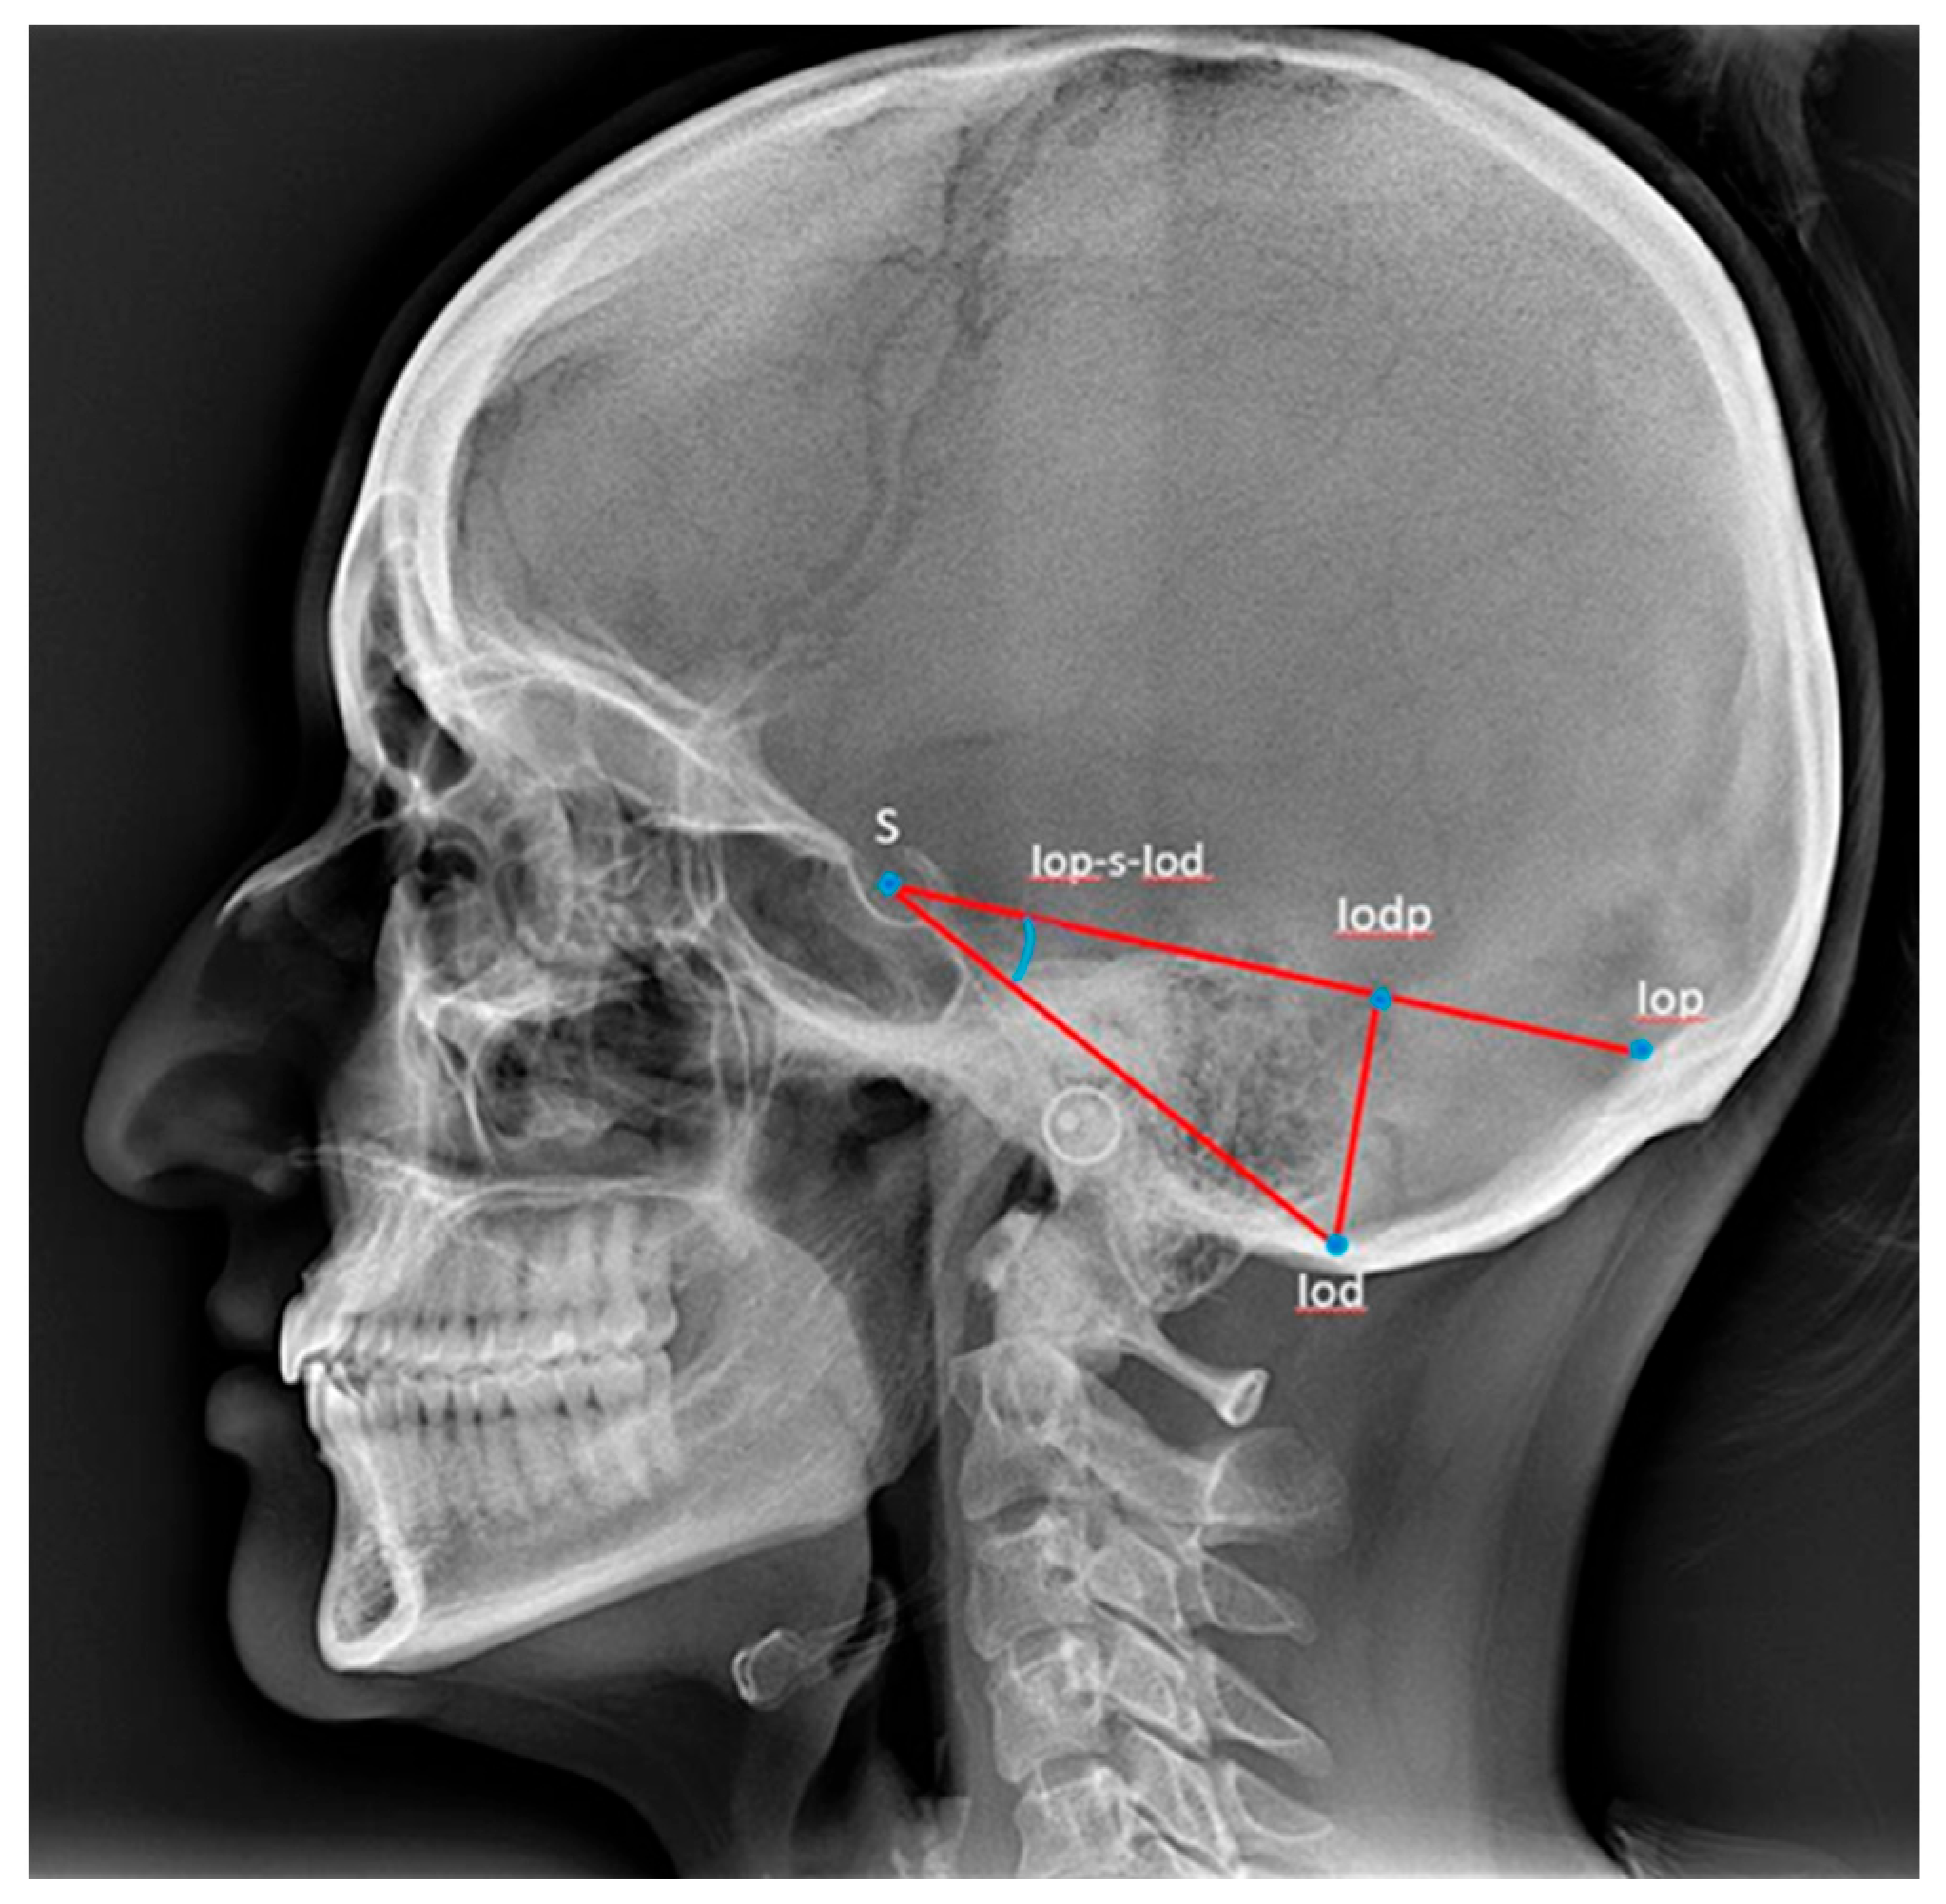

2.2.1. Cephalometric Analysis of Lateral Cephalograms

| Posterior cranial fossa dimensions | |||||||||||

| Iodp-iop (mm) | 51 | 26.9 | 50.4 | 37.75 | 5.34 | 74 | 27.7 | 49.3 | 34.66 | 3.95 | 0.044 *c |

| Iodp-iod (mm) | 51 | 19.9 | 41.0 | 33.7 | 3.73 | 74 | 25.2 | 36.4 | 31.02 | 2.55 | ˂0.001 *** |

| Iop-s-iod (Degrees) | 51 | 22.4 | 37.6 | 29.1 | 3.70 | 74 | 23.3 | 34.1 | 28.29 | 2.59 | 0.062 |

| s-iod (mm) | 51 | 58.7 | 80.2 | 70.13 | 4.72 | 74 | 58.7 | 76.3 | 65.66 | 3.65 | 0.001 ***a |

| s-iop (mm) | 51 | 85.2 | 118.9 | 98.99 | 7.31 | 74 | 82.3 | 106.4 | 92.47 | 4.91 | 0.003 **ab |